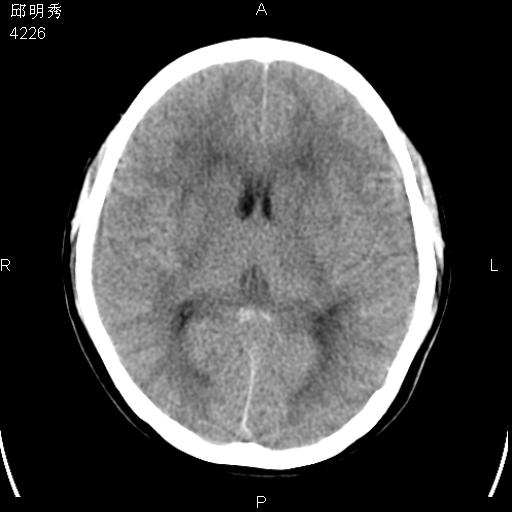

40f头晕十多天,右上肢麻木一天

脑白质变性或ms

脑白质脱髓鞘改变。

脑白质病;建议行mri检查。